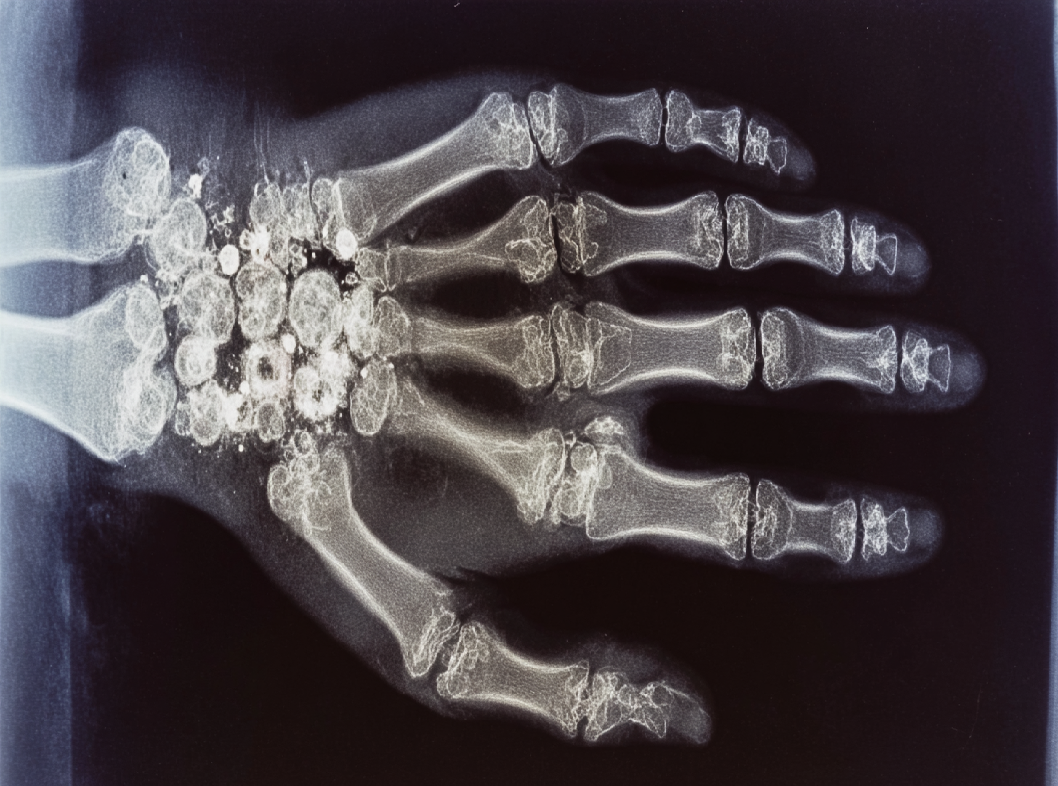

Рентгенография. Рентгеновские снимки позволяют врачам визуализировать структуру костей и выявить изменения в полулунной кости. В ранних стадиях заболевания изменения могут быть не так заметны.

- Хирургическое вмешательство. В случаях, когда консервативные методы не приносят достаточного улучшения, может потребоваться хирургическое лечение. Опции включают в себя артроскопию, резекцию (удаление части кости) или трансплантацию костной ткани.

- Трансплантация костной ткани. В некоторых случаях может потребоваться трансплантация костной ткани для восстановления поврежденной области полулунной кости.